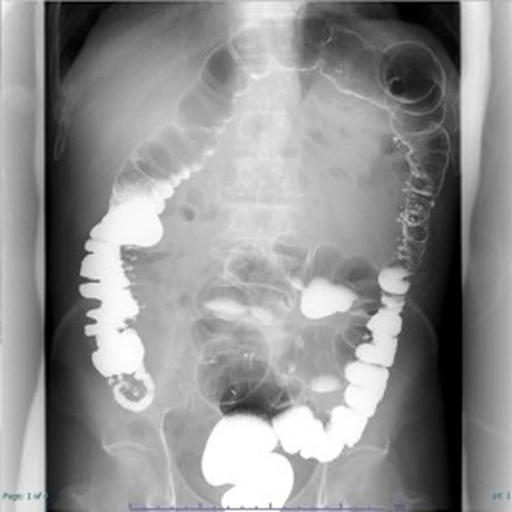

〇リアルタイムに写し出される動画を観察し、撮影するX線透視撮影装置です。

〇様々な部位(胃・小腸・大腸、肝胆膵臓系、肺および脊椎・四肢)で、検査および治療に利用されます。

〇造影剤を利用して目的部位を観察することもあります。